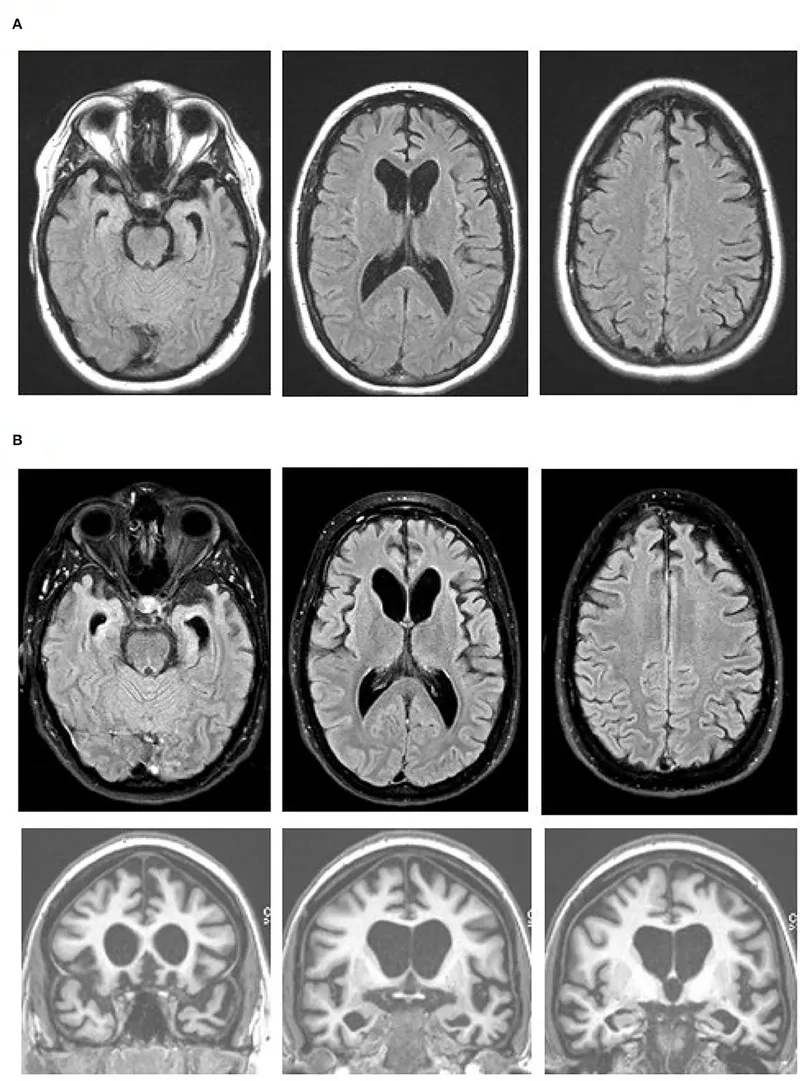

The most searched for Frontotemporal Dementia images

A visual guide to the stages of FTD

Key differences between FTD vs Alzheimer's